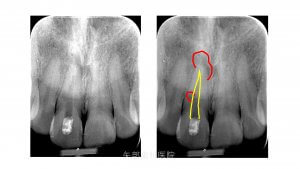

レントゲン所見

レントゲン所見を見てみると根尖部に限局した透過像が認められ、遠心歯根中央部に円形の透過像が認められます。根管と連続しているようにも見え、遠心歯根膜腔も途切れておらず歯根中央部に近接する歯槽骨に透過像は及んでいないように見えます。